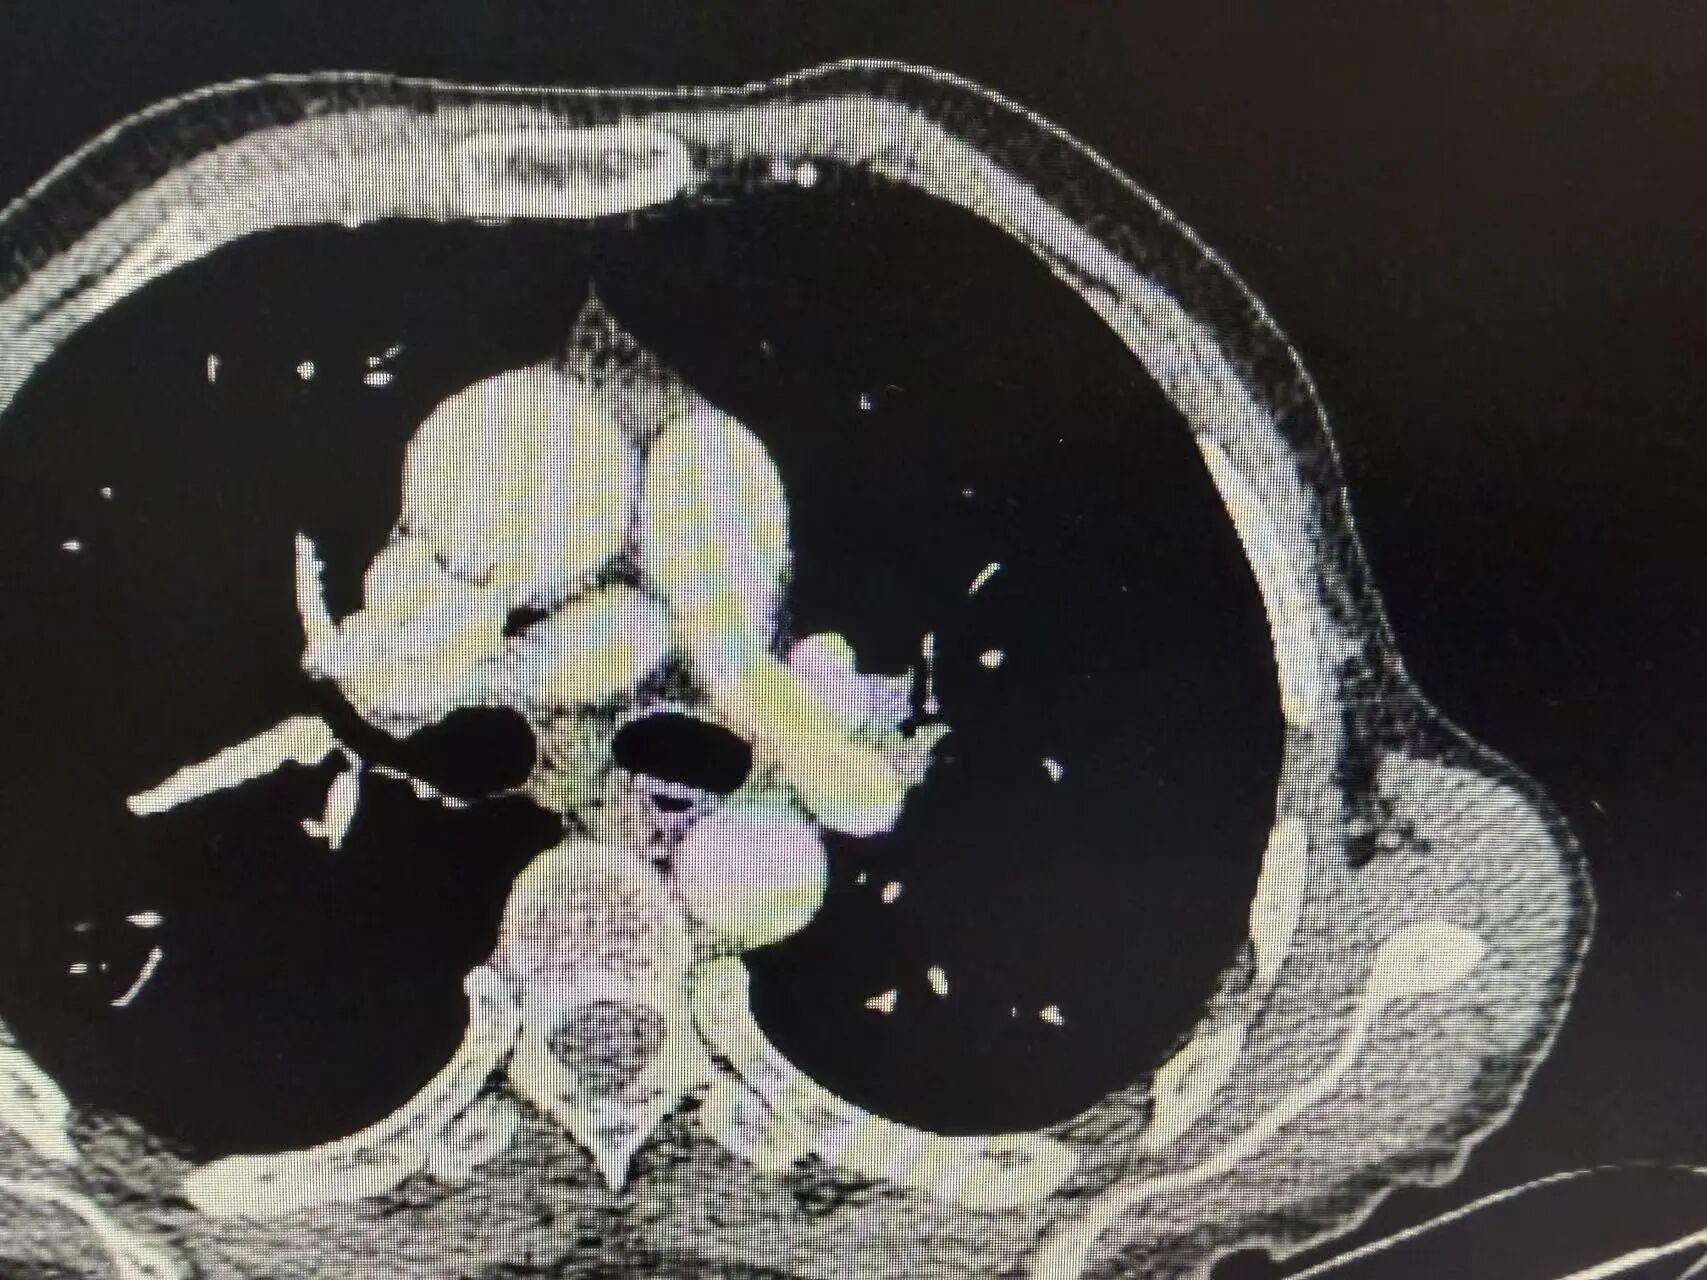

几个周期的治疗结束后,复查CT的结果传来了好消息:肿瘤明显缩小,原本粘连的血管也逐渐松动!这意味着,王叔终于获得了宝贵的手术机会,曾经的“不可切”,如今变成了“可切”。

新辅助治疗后CT:肿瘤明显缩小